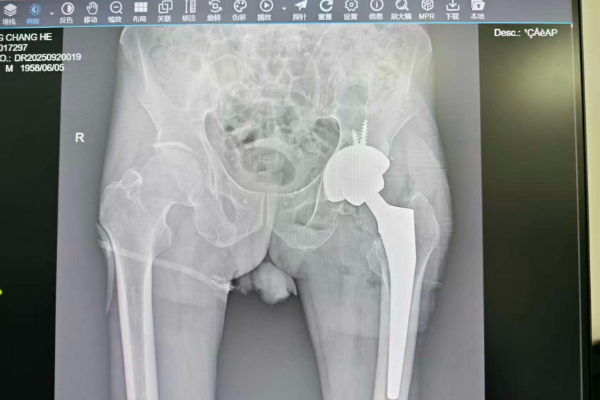

患者韦某,67岁,因髋关节置换术后脱位、疼痛及无法负重入院。经检查,其关节功能严重受损,肢体短缩,需实施髋关节翻修术。此类手术涉及假体取出、骨缺损修复及新假体安装,术中出血量大、操作复杂,对医院多学科协作和应急能力提出极高要求。

术前,专家团队通过三维CT等影像技术精准评估假体位置及骨缺损情况,制定个性化方案;术中,顺利完成髋臼及股骨侧假体取出、植骨填充及新假体精准安装,手术出血量少、耗时短于预期。术后,患者生命体征平稳,疼痛显著缓解,次日即可在助行器辅助下下地行走,恢复效果达到预期。